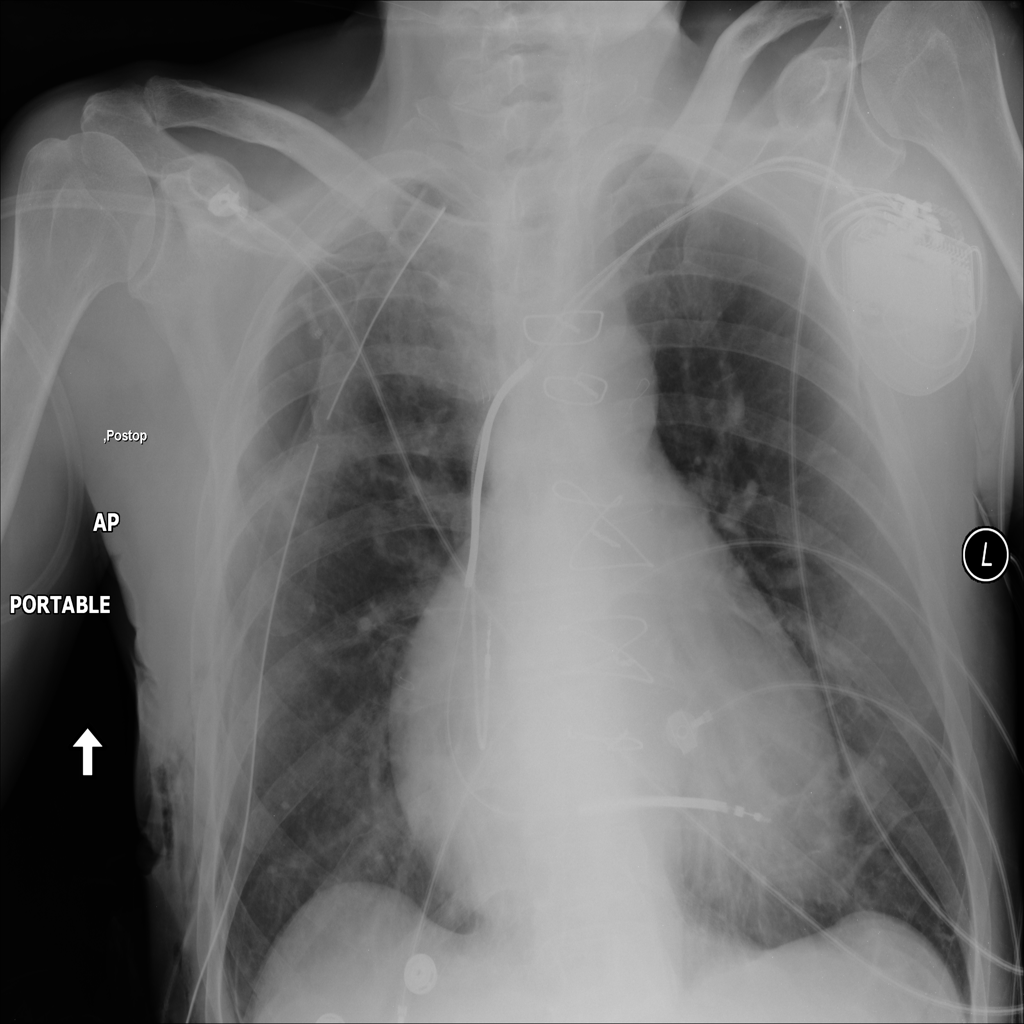

Dataset 2 – ChestX-ray14

The dataset contains 112’120 X-ray scans associated to 14 different labels [2]. The data is split according to the original patient-level data splits which results in 70% training, 10% validation and 20% test sets. We resize images to 512x512 pixels and optimize the network using the Adam optimizer [12]. In this case, we compare the weighted cross-entropy loss and add the weighting term to the class labels due to the significant class imbalances in the data (i. e., weights are equal to the inverse class occurence). For all experiments we use a DRND-54 [10] CNN as the base architecture. We fix the hyperparamters and find the best bandwidth using cross-validation ().

Results of our AS-MLC method are given in Table 2 and yield a 0.8008 mean AUC. Our method thus outperforms the softmax cross entropy loss by nearly 3% in mean ROC values. These results using a standard network are in range of previously published state-of-the-art results that used large amounts of additional training data [13] (0.806), attention based models [14, 15] (0.8027 and 0.816) and significantly outperform the original publication [2].